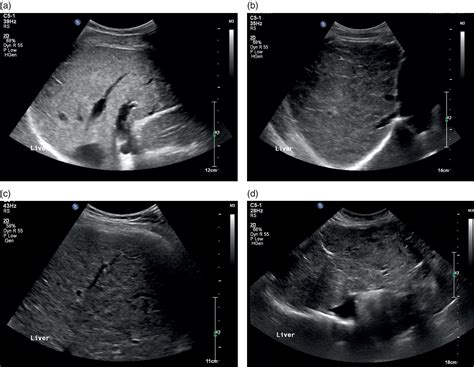

What Does a Normal Liver Ultrasound Look Like?

A radiologist interprets the scan by evaluating several key characteristics of the liver tissue and surrounding structures. When a report states a normal liver ultrasound, it means the following findings were observed:

Feature Expected Normal Finding

Size The liver should be of normal proportions, not enlarged (hepatomegaly) or shrunken (atrophy).

Echogenicity The texture should be uniform and slightly brighter than the adjacent kidney cortex.

Contours The edges should be smooth, not irregular or nodular.

Vessels Hepatic veins and the portal vein should be visible, patent, and show normal blood flow patterns.

Biliary Ducts Should not be dilated or obstructed.